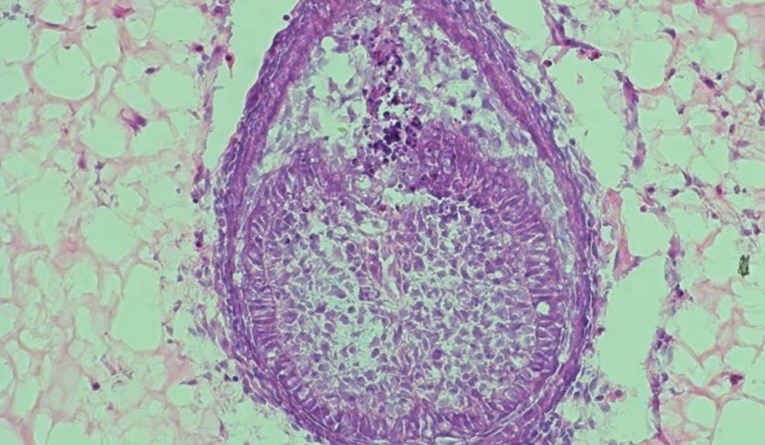

To okruženje, koje znanstvenici nazivaju “skelom”, ključno je za uspjeh. U najnovijoj studiji, umjesto kolagena korištenog 2013., tim sada koristi hidrogel, polimer s visokim udjelom vode. “Prvo prikupljamo stanice iz mišjih embrija, zatim ih miješamo i centrifugiramo kako bismo dobili malu staničnu kuglicu. Zatim ubrizgavamo tu kuglicu u hidrogel i uzgajamo je oko osam dana”, objasnio je Xuechen Zhang, doktorand na King’s Collegeu i koautor studije. Nakon osam dana, unutar hidrogela formiraju se strukture nalik zubima. U prethodnom istraživanju, takvi “zubni zameci” preneseni su u miša gdje su se razvili u zubnu strukturu s korijenom i caklinom.